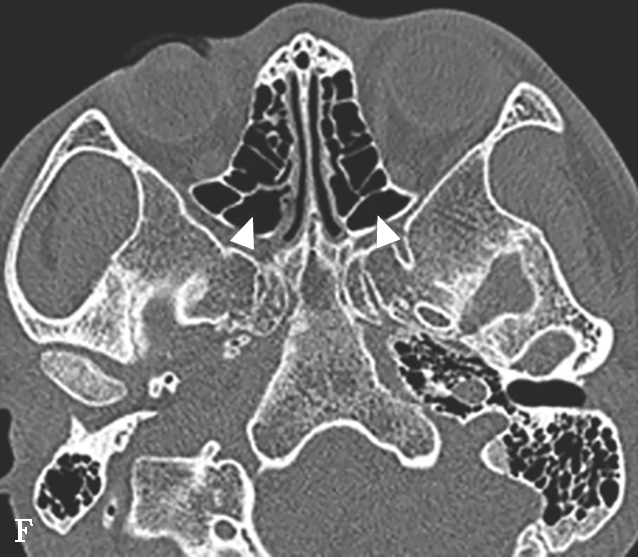

蝶窦常见解剖变异包括:①有分隔的蝶窦,可为纤维或骨性分隔分成几个不对称的部分,此变异容易导致蝶窦手术引流不完全而残留病变;②介甲型蝶窦,窦腔略有气化,发育很小,窦腔后缘与鞍结节垂直线之间尚有10mm厚骨质;③鞍前型蝶窦,蝶窦发育较小,窦腔后缘与鞍结节垂直线相齐,恰好位于蝶鞍之前,蝶鞍底大部分为松质骨;④半鞍型蝶窦,发育尚好,后上缘占鞍底前半部;⑤全鞍型蝶窦,发育良好,自鞍结节至鞍背连线的全鞍底与蝶窦只一层薄骨板;⑥枕鞍型蝶窦,与全鞍型相似,但发育更大,后缘超过鞍背垂线,蝶窦侵入枕骨使斜坡骨板更薄(图1-3-7)。

图1-3-7 蝶窦及蝶窦区解剖变异

A.颈内动脉管突入蝶窦;B.蝶窦间隔(白箭);C.左侧翼突气化;D.蝶嵴(星)、蝶骨大翼(白箭)、鞍背气化(虚箭);E.蝶骨小翼气化(白箭);F、G.鞍前型蝶窦(三角);H、I.甲介型蝶窦;J、K.鞍型蝶窦;L.Odoni气房(白箭)